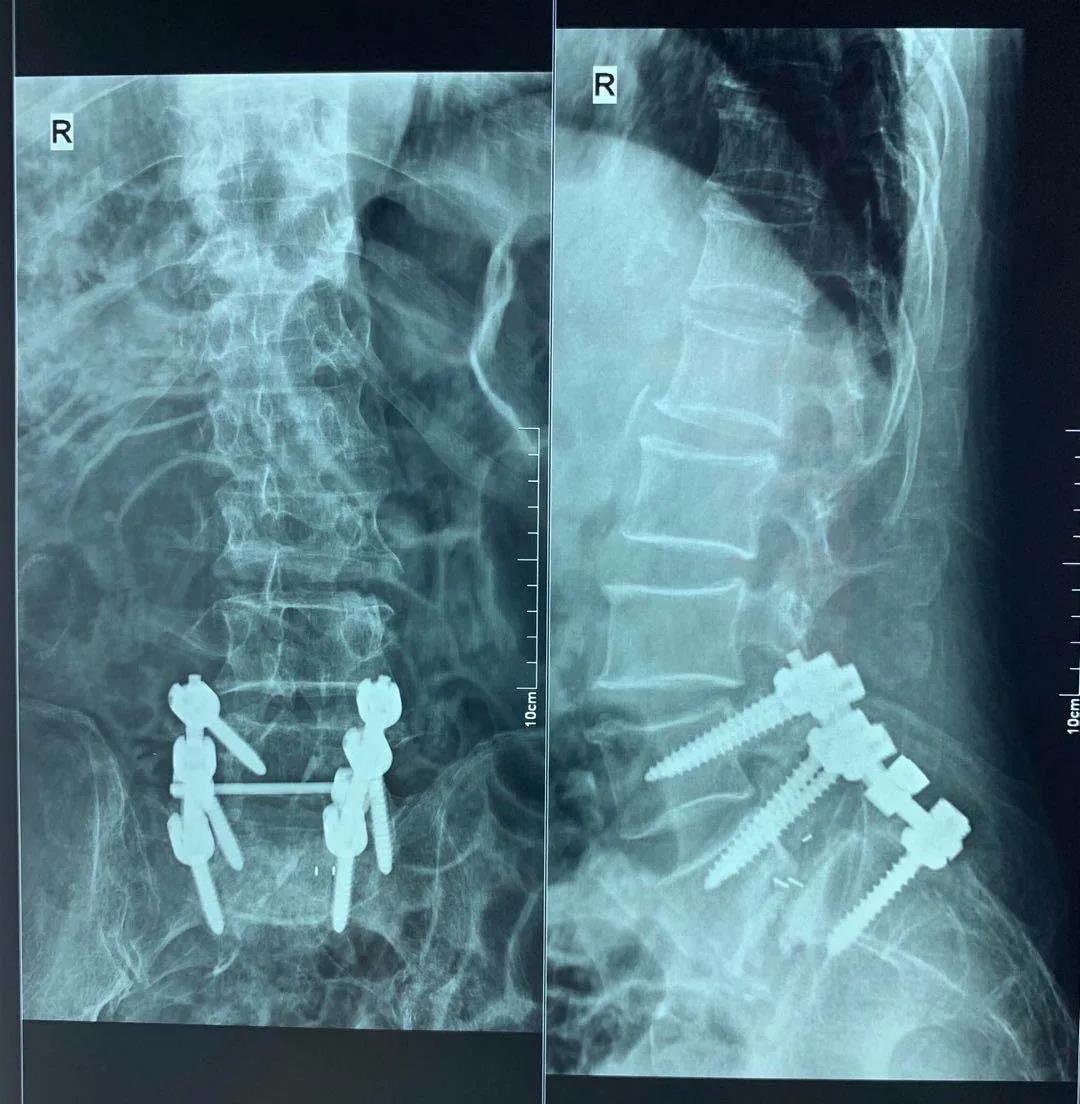

近日,醫(yī)院骨二科成功完成復雜腰椎內固定翻修手術一例,患者為77歲老年男性,因腰椎滑脫(3度)于2020年5月2日在外院行腰椎后路滑脫復位內固定及椎間融合術,術前患者能自行行走,術后出現(xiàn)腰痛及下肢后側疼痛,并雙髖及雙膝關節(jié)屈曲伸直活動受限,伸直受限于屈曲110°位,經外院康復理療不能好轉,于2020年6月4日來醫(yī)院骨二科就診。骨二科主任許冬雷為其進行了X線檢查,檢查提示腰椎滑脫內固定裝置失效導致再次滑脫,并椎間融合器部分脫出至椎管,給予收住院治療,完善腰椎CT及頸椎磁共振,并組織科內討論,詳細查體及仔細研讀影像學資料。

手術前后對比

手術前

手術后

科室綜合分析患者現(xiàn)在的病情,考慮手術內固定失效是引起癥狀的主要原因,決定給予行腰椎滑脫內固定翻修術,在院領導、麻醉科和手術室的支持下,充分論證手術可能存在的風險及相關處理方案,向患者及家屬詳細的介紹病情及治療方案,取得患者及家屬的同意,完善術前準備,骨二科許冬雷專家團隊于6月23日全麻下行腰椎滑脫內固定失效翻修術,術中給予去除移位的椎間融合器,更換腰5左側的椎弓根螺釘,考慮患者為骨質疏松患者,更換的椎弓根釘為骨水泥型椎弓根釘,并考慮患者單純骶1螺釘固定應力較大,給予增加左側髂骨釘固定,術中透視確認內固定位置,手術順利,患者入ICU監(jiān)護治療,術后第一天患者自述腰痛及下肢疼痛消失,雙下肢自主活動及感覺正常,雙膝伸直受限明顯好轉,可伸直至80°,術后三天出ICU返回病房,給予復查X線平片及CT檢查,見滑脫椎體大部復位,并更換的椎弓根螺釘及髂骨釘位置良好,繼續(xù)給予理療及功能鍛煉,現(xiàn)能主動伸直至膝關節(jié)屈曲60°位,下一步擬患者腰部手術恢復后行頸椎微創(chuàng)射頻治療,緩解患者的髖膝周圍肌肉張力,進一步緩解患者的髖膝關節(jié)功能。